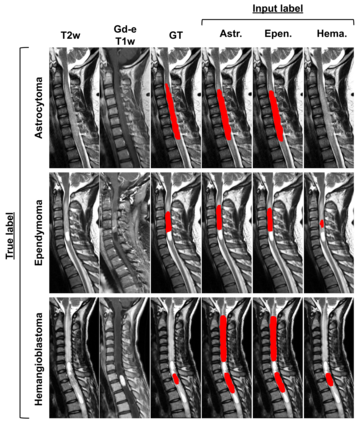

Medical images are often accompanied by metadata describing the image (vendor, acquisition parameters) and the patient (disease type or severity, demographics, genomics). This metadata is usually disregarded by image segmentation methods. In this work, we adapt a linear conditioning method called FiLM (Feature-wise Linear Modulation) for image segmentation tasks. This FiLM adaptation enables integrating metadata into segmentation models for better performance. We observed an average Dice score increase of 5.1% on spinal cord tumor segmentation when incorporating the tumor type with FiLM. The metadata modulates the segmentation process through low-cost affine transformations applied on feature maps which can be included in any neural network's architecture. Additionally, we assess the relevance of segmentation FiLM layers for tackling common challenges in medical imaging: multi-class training with missing segmentations, model adaptation to multiple tasks, and training with a limited or unbalanced number of annotated data. Our results demonstrated the following benefits of FiLM for segmentation: FiLMed U-Net was robust to missing labels and reached higher Dice scores with few labels (up to 16.7%) compared to single-task U-Net. The code is open-source and available at www.ivadomed.org.